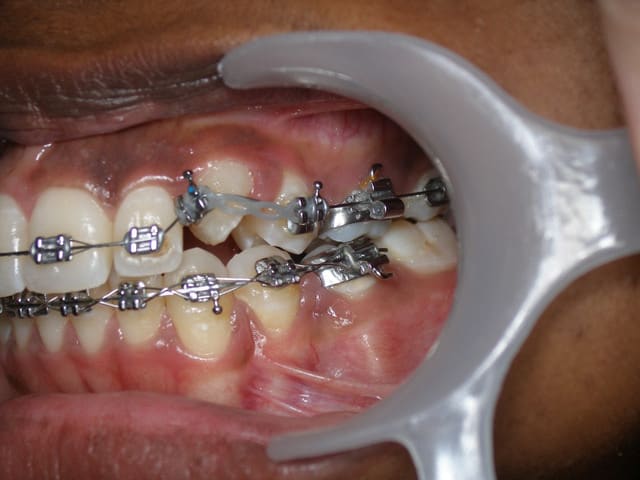

Pour info, il est préférable :

1. de faire le collage avec un anneau ou bouton à bords mousses, afin de limiter le traumatisme de la gencive. Le bracket sera positionné en supra-gingival. Il est de toute façon quasiment impossible de le placer correctement en première intention.

2. d'utiliser un auxiliaire métallique ( ligature avec toron, chainette or...) dans la partie sous muqueuse et de réserver la chainette ou fil élastomérique à la zone supra-gingivale.